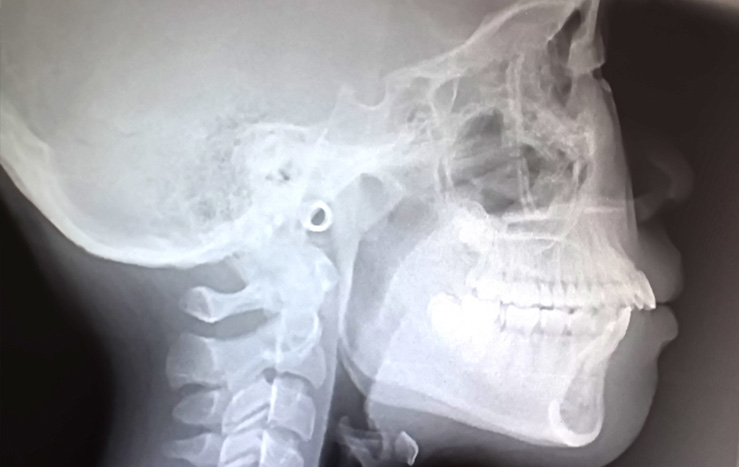

通常のレントゲンとは違い、歯や顎の骨の位置を3Dによる立体的な画像で確認することができます。

頭部を正面と側面から撮影することで顔の骨格を詳しく把握することができます。

お口や骨格の状態などを詳しく知るために、歯科用CTやセファロレントゲン、口腔内スキャナーを使用した精密検査を行います。矯正検査には費用がかかるので、まずはお問い合わせください。